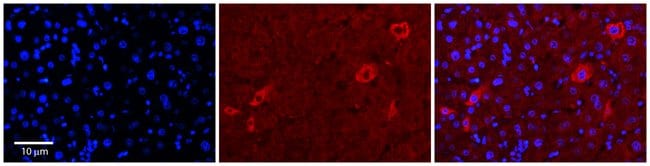

Immunogen sequence: MGSGCRIECI FFSEFHPTLG PKITYQVPED FISRELFDTV QVYIITKPEL For short term use, store at 2-8°C up to 1 week. For long term storage, store at -20°C in small aliquots to prevent freeze-thaw cycles. Predicted homology: Cow: 100%; Dog: 100%; Guinea Pig: 100%; Human: 100%; Mouse: 100%; Rabbit: 100%; Rat: 100%; Zebrafish: 100%.

NPRL2, also known as TUSC4 (tumor suppressor candidate 4), is a 380 amino acid protein that contains a bipartite nuclear localization signal and a granulin protein-binding domain. It is highly expressed in skeletal muscle, followed by brain, liver and pancreas, with lower expression in lung, kidney, placenta and heart. NPRL2 is also expressed in most lung cancer cell lines and may be involved in tumor suppression. NPRL2 may play a role in mismatch repair, cell cycle checkpoint signaling and activation of apoptotic pathways. It may also enhance the therapeutic efficacy of chemotherapy drugs such as cis-platin by resensitizing patients resistant to cisplatin treatment. The gene encoding NPRL2 is conserved between species and is expressed as two isoforms due to alternative splicing events.